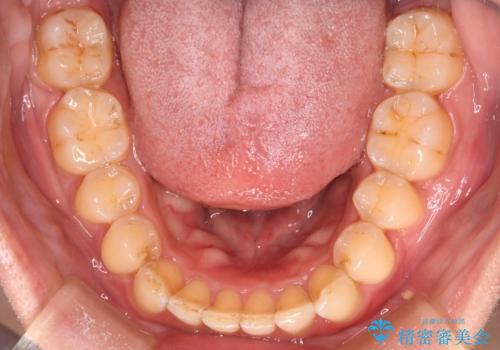

- 下の歯のがたつきを主訴に来院されました。

下の歯のがたつきと右の奥歯の噛みあわせ改善するために治療計画を立てることにしました。

下の前歯のがたつき改善にはIPR(歯と歯の間を削る処置)を行いました。